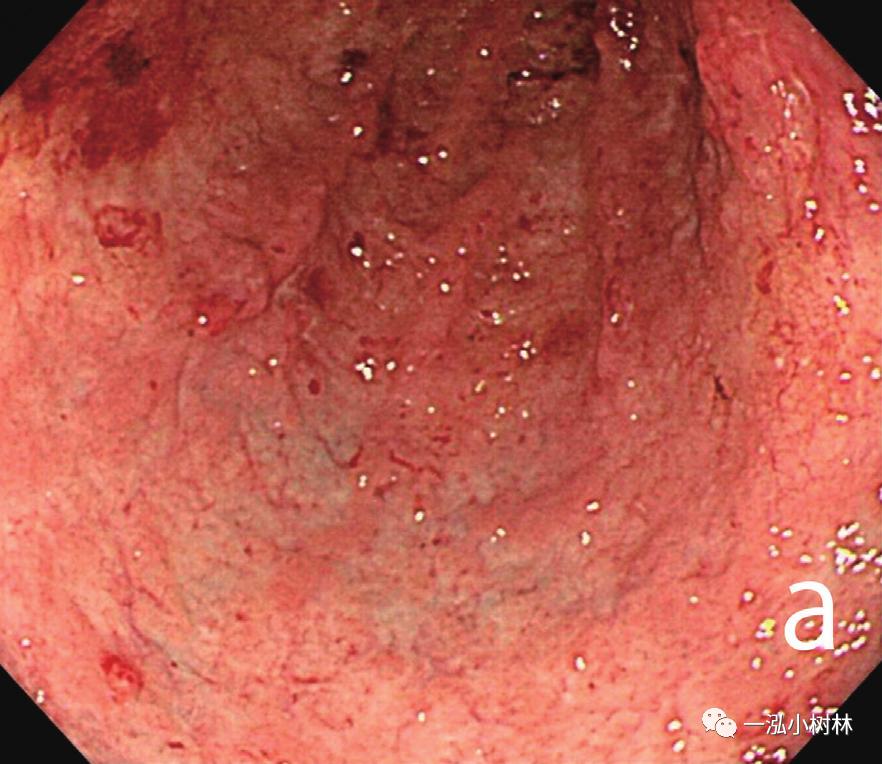

内镜检查(图1):胃黏膜整体粗糙、弥漫性隆起,易出血。在胃体下部、胃窦部黏膜的粗糙明显,散在小隆起,一部分也发现了较大的隆起性变化。ME-NBI观察即使残留着接近正常的腺管,表面微细结构的消失也很明显,在褪色区域也发现了血管的扩张和蛇行、腺管结构的紊乱。

图1a 白光内镜 胃体下部黏膜整体粗糙、易出血性,发红和褪色混合存在。

白光内镜:细颗粒样外观,黏膜质脆、糜烂(H-260Z)